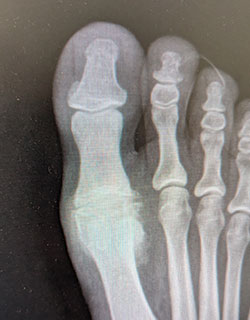

Hallux rigidus (severe arthritis of the big toe joint) causing painful, limited motion of the joint and requiring removal of the arthritic bone and partial joint replacement (hemi-arthroplasty) to allow full range of motion and return to weight bearing.

Before SurgeryBefore

After SurgeryAfter